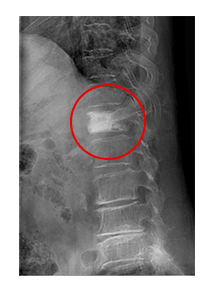

의사는 등과 허리검사와 진단을 위해 환자의 병력과 기저질환을 탐색하고, 이학적 검사와 신경학적 검진을 시행합니다. 단순 X-ray 촬영을 통해 간단하게 골절여부가 확인되지만 골절의 정도가 심하지 않거나, 다친 경험이 정확하지 않은 경우에는 정밀검사가 필요하기도 합니다.

또한, 신경손상등의 다른 심한 손상이 동반된 척추골절 분류에 포함되는지 확인하기 위해 허리검사 CT나 MRI 등의 정밀검사를 시행하기도 합니다. 급성 압박골절의 경우에는 허리 골절 수술을 시행하지 않더라도 MRI의 급여 적용이 가능합니다.